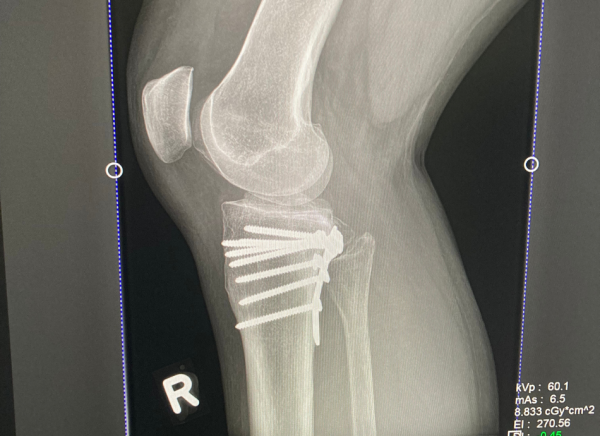

The most common way to diagnose a fracture is by an x-ray. An x-ray shows the type of fracture and its location within your bone. Sometimes an MRI or a CT scan may be needed.

- A more severe fracture may need surgery to insert pins, plates or screws to hold your bone in place.

Image credit: Healthify He Puna Waiora, NZ, 2023